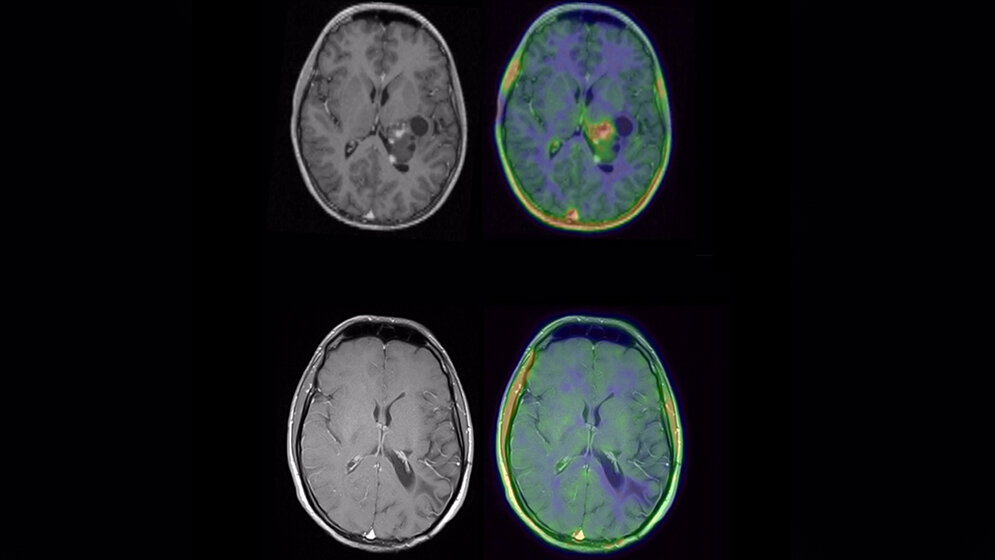

*Ergänzung zur Abbildung:

MRT eines Patienten mit Glioblastom vor (oben) und nach (unten) molekularer neuropathologischer Diagnostik und zielgerichteter Therapie. Die Wilhelm Sander-Therapieeinheit NeuroOnkologie ermöglicht neben einer gezielten Diagnostik auch die personalisierte Behandlung von Patienten mit Hirntumoren.